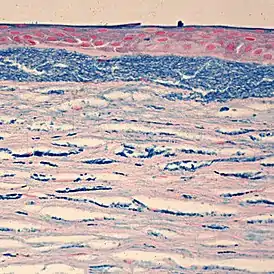

![]() Окрашивание на гликозаминогликаны отчётливо выявляет изменения структуры роговицы - отложения внутри кератоцитов и во внеклеточном пространстве под эпителием | |

Гистопатологически болезнь характеризуется сниженной толщиной роговицы, предположительно из-за более плотного расположения коллагеновых фибрилл, и накоплением гликозаминогликанов в кератоцитах и эндотелиальных клетках наряду с внеклеточными отложениями того же материала в толще стромы и десцеметовой мембране, в заднем слое которой образуются капли (англ. guttae).